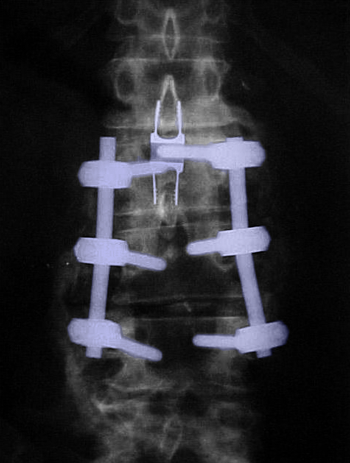

Οσφυϊκή σπονδυλοδεσία Ο3-Ο5. Βίδες στα σώματα των σπονδύλων (πράσινο βέλος) ενωμένες με ράβδους (φούξια βέλος). Συνδετική γέφυρα με κυανό βέλος.Περιοχή της πεταλεκτομής με κόκκινο περίγραμμα. |